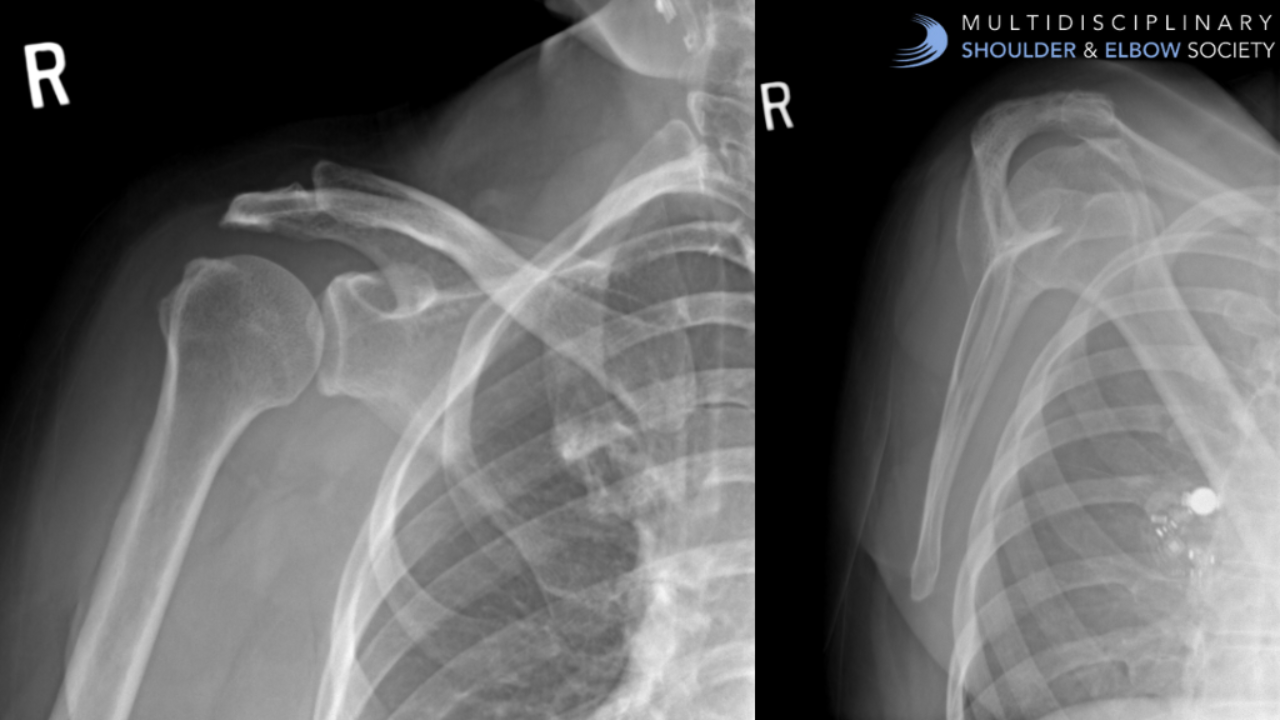

Case Study: 24M Recurrent Shoulder Instability case study quiz question shoulder dislocation shoulder instability traumatic anterior shoulder dislocation

A computed tomography image of a 24-year-old banker who has recurrent shoulder instability demonstrates 6% bone loss of his glenoid. His first dislocation occurred as a teenager while snowboarding. Th...

Case of the Week: Atraumatic Lateral Shoulder Pain in a 59F case of the week case study rotator cuff related pain subacromial impingement

Case of the Week: Atraumatic Lateral Shoulder Pain in a 59F

CC: Atraumatic Lateral Shoulder Pain in a 59F.

HPI: This 59-year-old female has had a 1 year atraumatic history of lateral shoulder pain. ...